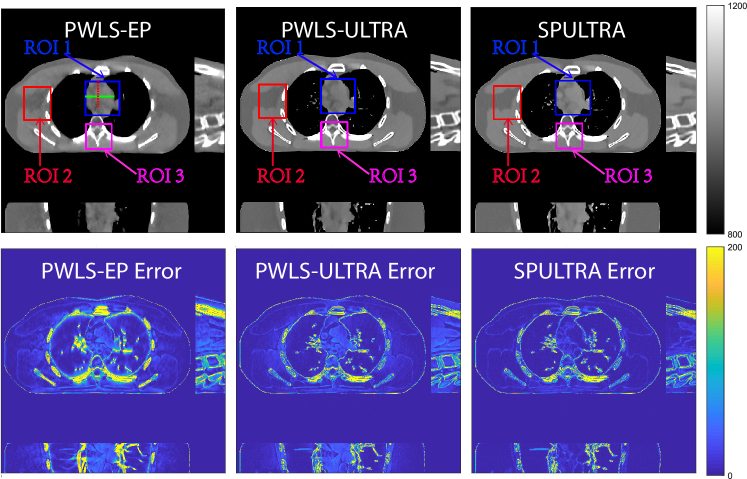

Refer to caption

(a)

(b)

Figure 4: Comparison of reconstructions and reconstruction errors at (a) I0=3×103subscript𝐼03superscript103I_{0}=3\times 10^{3} and (b) I0=2×103subscript𝐼02superscript103I_{0}=2\times 10^{3} dose levels. The 3D images are displayed with the central slices along the axial, sagittal, and coronal directions. The unit of the display windows is HU.

(a) I0=3×103subscript𝐼03superscript103I_{0}=3\times 10^{3}

(b) I0=2×103subscript𝐼02superscript103I_{0}=2\times 10^{3}

Figure 5: 3D displays of reconstructions of ROI 1 defined in Fig. 4. The display windows are [900, 1200] HU.

V-A5 Visual Results and Image Profiles

Fig. 4 shows the reconstructed images and the corresponding error images for PWLS-EP, PWLS-ULTRA, and SPULTRA, at I0=3×103subscript𝐼03superscript103I_{0}=3\times 10^{3} and I0=2×103subscript𝐼02superscript103I_{0}=2\times 10^{3}. Compared to the PWLS-EP result, both PWLS-ULTRA and SPULTRA achieved significant improvements in image quality in terms of sharper reconstructions of anatomical structures such as bones and soft tissues, and suppressing the noise. However, the PWLS-ULTRA method introduces bias in the reconstructions, which leads to larger reconstruction errors compared to the proposed SPULTRA method. In Fig. 4, we marked three 3D ROIs in the axial plane, i.e., ROI 1, ROI 2, and ROI 3. Fig. 5 shows the zoom-in images of a 3D plot of ROI 1, and those of ROI 2 and ROI 3 are shown in the supplement. We also plot the evolution of RMSE through the axial slices of the three 3D ROIs in Fig. 6. The figures demonstrate that SPULTRA clearly outperforms the competing PWLS-EP and PWLS-ULTRA schemes.

The above advantages of SPULTRA can be seen more clearly when observing the image profiles. Fig. 7 plots the image profiles for the three methods together with that of the ground-truth image. Fig. 4 shows the horizontal green solid line and the vertical red dashed line, whose intensities are plotted in Fig. 7. It is obvious that the profiles for SPULTRA are closest to the ground-truth among the three compared methods. The gap between the profiles of the PWLS-based methods and the ground-truth shows the bias caused by the compared PWLS methods.